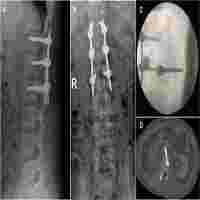

Presentation and management of IVC and iliac vein encroachment by lumbar pedicle screws: a case-report

| Abstract | Pedicle screws are commonly used in spinal surgeries and are relatively safe, with venous complications occurring rarely. We report a patient with imaging following a L4–5 fusion that showed indentation of the inferior vena cava and right common iliac vein by the right L4 and L5 pedicle screws. She underwent revision surgery in which the hardware was removed and no bleeding was observed. Intraoperative venogram confirmed vascular integrity and absence of indentation on the venous structures following screw removal. The patient recovered without complications. Venous contact by pedicle screws should be treated on a case-by-case basis in a multidisciplinary approach with vascular surgery. We discuss a treatment algorithm for the operative management of this problem. |